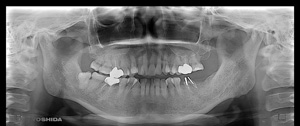

K‚³‚ñ @‚U‚QÎ —«@@Žå•w@@Žèp“ú ‚Q‚O‚O‚X”N ‚VŒŽ ‚V“úi‰Îj @‰ºŠ{ƒm[ƒxƒ‹ƒKƒCƒhŽg—p@Ö¬“à’ÁÕ¹—pišq“f”½ŽË‚ª‹­‚¢‚½‚ßj

@@@     @‰ºŠ{ ‚Q–{    ’x‰„‰×d@”‚S‚TE‚S‚U•” @

Rpl Tapered Rp ~ ‚P‚O mm  @ Rpl Tapered Wp ~ ‚P‚O mm